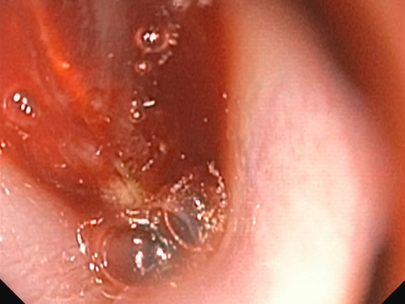

当院受診の3日前より、黄色い液体を5?6回連続で嘔吐し、その後より鼻出血および両側鼻腔の通気性低下が認められたとのことで、まず他院を受診されました。 その際に実施されたレントゲン検査では明らかな異常は認められなかったとのことです。 当院にて再度胸部および頭部のレントゲン検査を実施したところ、呼気時における咽喉頭部の一過性の拡張所見が認められましたが、骨の破壊などの明らかな構造的異常は確認されませんでした。 症状の急性発症であること、ならびに鼻閉および鼻出血を伴うことから、鼻腔・鼻咽頭内の異物の存在を強く疑い、同日にCT検査および内視鏡検査を実施しました。 検査の結果、鼻腔から鼻咽頭内にかけて毛玉と思われる異物を認めたため摘出を行ったところ、呼吸状態や全身状態は速やかに改善し、当日中に退院となりました。 その後の経過も良好で、現在までに1年が経過していますが、症状の再発は認められていません。

レントゲン画像で骨破壊等を評価

左・下:CT検査にて腫瘍性疾患の否定